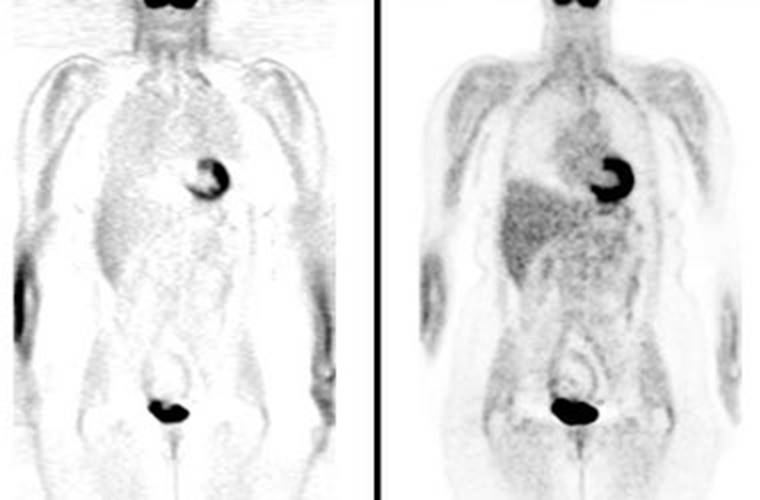

Figure 1 - Attenuation correction: The images below are from

the same patient. The image on the left is non-attenuation corrected (the lungs

and skin surface appear warm). The right image is corrected for attenuation.

Note the improved visualization of structure